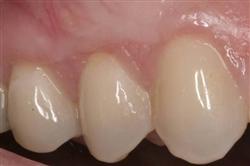

Functional Soft Tissue Grafting

Normally gum tissue surrounds and protects the delicate roots of your teeth. Exposed tooth roots are prone to tooth decay, root canals, discoloration and actual jawbone loss. All of this can lead to tooth loss in advanced cases.

Functional Soft Tissue Grafting replaces the missing gum tissue and protects your teeth. For this reason, soft tissue grafting may be recommended even for back teeth.